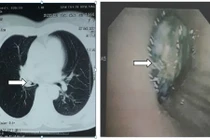

| Dị vật được lấy ra là một bóng đèn led, đường kính chỉ vài li nhưng có những chấu sắt găm sâu vào phổi. |

Bệnh nhi Trần Hoàng L. (6 tuổi, ngụ Tiền Giang) nhập viện ngày 18/12 trong tình trạng thở khò khè, hơi thở hôi, ho kéo dài. Bác sỹ Nguyễn Kinh Bang, Phó trưởng khoa Ngoại tổng hợp cho biết, sau khi chụp X-quang, phát hiện dị vật là một bóng đèn led đồ chơi có kích thước 3x4mm còn nguyên 2 chân móc sắt bám chặt vào niêm mạc phế quản khiến khu vực này sưng phù nề. Tuy nhiên, các bác sỹ không thể gắp được dị vật vì khu vực nhiễm trùng sưng to và chảy máu nhiều, buộc phải dừng nội soi để điều trị kháng sinh.

Bác sĩ Nguyễn Kim Bang cho biết, do phát hiện quá muộn nên dị vật gây biến chứng nhiễm trùng nặng trong phế quản. Các bác sỹ đã lấy dị vật ra và buộc phải cắt bỏ thùy dưới phổi do đã bị tổn thương quá nặng. Nếu phát hiện sớm, bệnh nhi đã không phải chịu cuộc mổ lớn và bảo tồn được phổi.